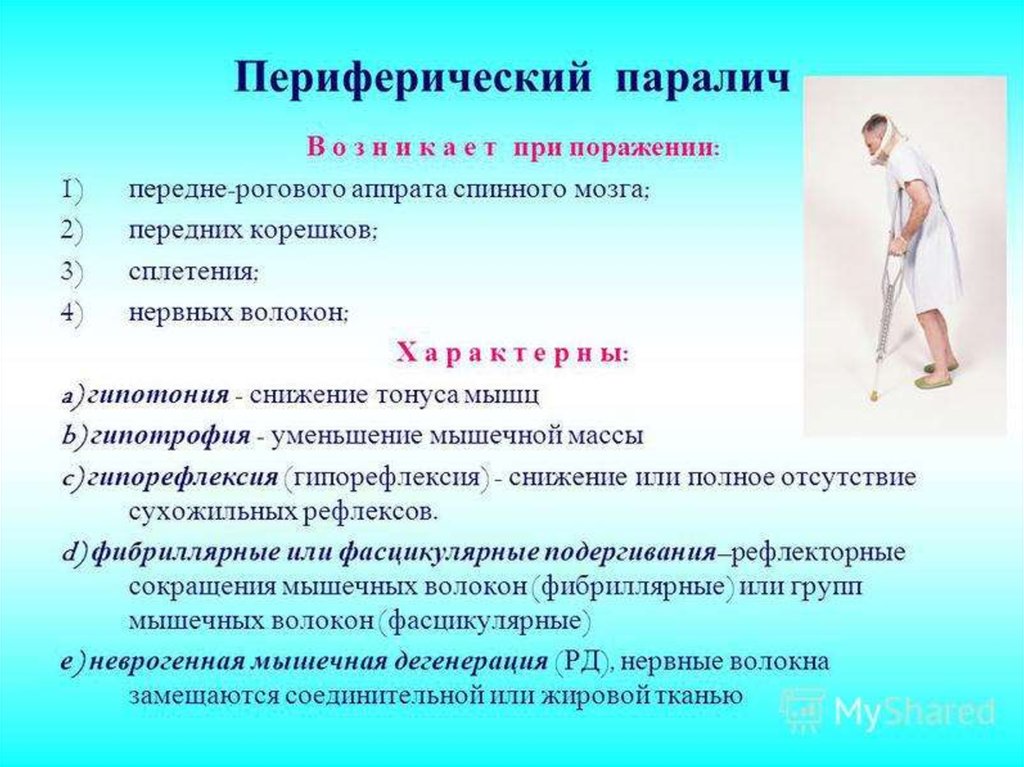

Пирамидная симптоматика в неврологии: ключевые аспекты